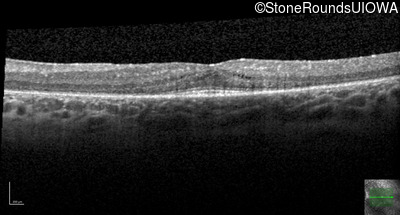

Optical Coherence Tomography - Left - 20/32 +1

Exemplar / OCT Stack

OCT Stack